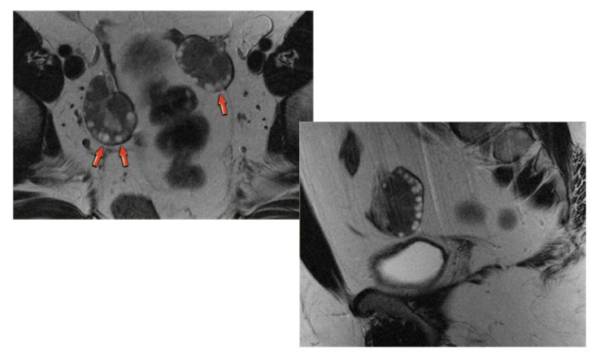

- УЗИ, которое позволяет точно определить размеры яичников, а также визуализировать наличие множественных кистозных новообразований;

- МРТ для исключения наличия опухолей в яичниках (снимок представлен на фото);